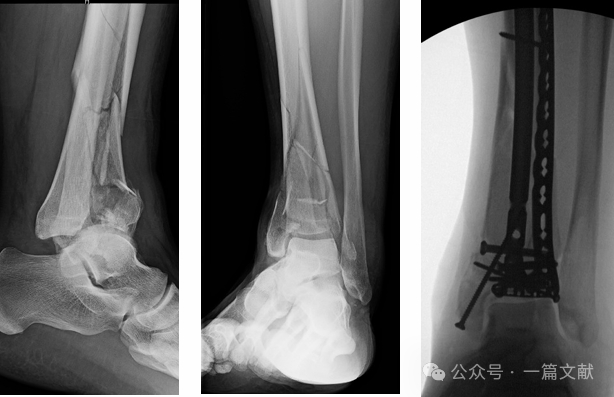

无关节面压缩,属于踝关节骨折向Pilon骨折过渡类型;

经皮腓骨骨折髓内固定可最大限度保留手术入路选择空间。如下图:

联合拉力螺钉及关节骨块钢板固定时,可为粉碎性骨折区域提供早期稳定性以促进愈合。如下图: